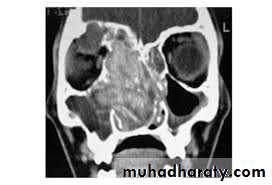

Investigation

4. CT- scan of the sinuses may show

microcalcification of opaque fungal mass in the

non-invasive form due to accumulated heavy

metals, e.g. calcium, manganese. There may be

evidence of bone expansion. The invasive type,

however, will show evidence of bone destruction

with spread of disease outside the sinuses. MRI

scanning may further help delineate fungal mucin

from reactive inflammation .